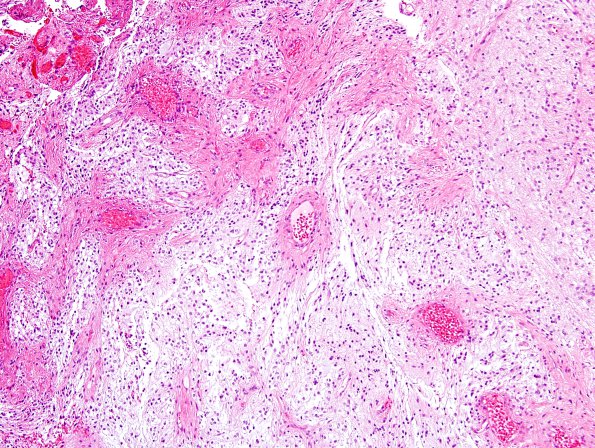

Astrocytoma, pilocytic - Microscopic

46A2 Astrocytoma, pilocytic (Case 46) H&E 16

Biphasic growth pattern.